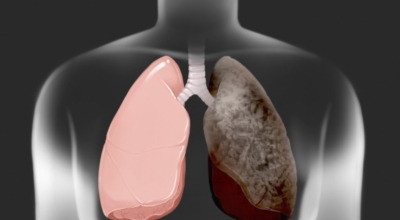

폐암의 원인 ① 흡연

폐암의 주요 발병 원인은 흡연입니다. 담배에는 많은 유해 물질과 암을 유발하는 성분들이 포함되어 있는데, 흡연자는 비흡연자에 비해 폐암 위험이 15배에서 80배까지 높아집니다. 특히 흡연량이 많거나, 어린 나이에 흡연을 시작했거나, 흡연 기간이 길수록 위험도는 더욱 커지게 됩니다.